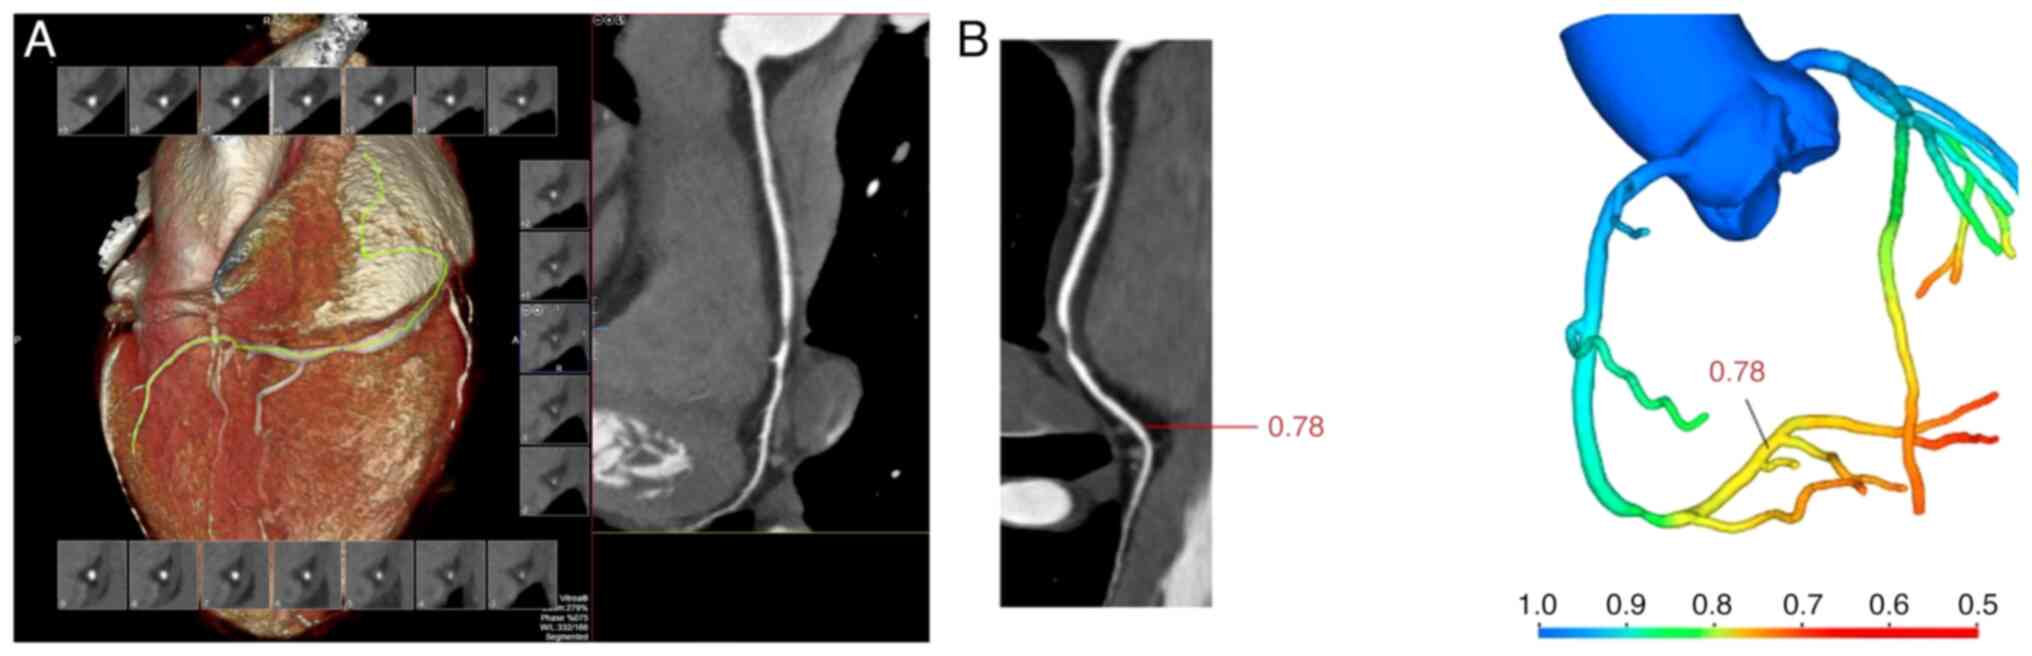

Value of CT‑derived fractional flow reserve in identifying patients with acute myocardial infarction based on coronary computed tomography angiography

The aim of the present study was to determine whether coronary stenosis and computed tomography‑derived fractional flow reserve (CT‑FFR), detected by coronary computed tomography angiography (CCTA), can potentially contribute to distinguish acute myocardial infarction (AMI) from unstable angina (UA). The study retrospectively collected data from consecutive patients who were admitted with obstructive coronary artery disease (CAD) and who received CCTA and invasive coronary angiography (ICA) as part of their clinical workup. According to the inclusion criteria, the patients were divided into the AMI group and UA group, and the basic clinical data, CCTA stenosis degree and CT‑FFR values were compared between the two groups. Univariate and multivariate logistic regression methods were used to analyze the association between ≥70% CCTA stenosis, ≤0.80 CT‑FFR and AMI. A diagnostic model of AMI was established (model 1, ≤0.80 CT‑FFR; model 2, ≥70% CCTA stenosis; and model 3, ≤0.80 CT‑FFR combined with ≥70% CCTA stenosis), and the diagnostic efficacy of the three models for AMI was compared. The significance level was set at P<0.05. A total of 116 participants were finally enrolled in this study. There were 37 patients in the AMI group, with an average age of 62.06±7.74 years, and 79 patients in the UA group, with an average age of 58.11±10.0 years; there was no significant difference in age (P>0.05). The multivariate regression analysis revealed that ≤0.80 CT‑FFR (HR=28.074; 95% CI: 5.712‑137.973; P<0.001), and ≥70% CCTA stenosis (HR=10.796; 95% CI: 2.566‑45.425; P=0.001) were independent risk factors for AMI. The diagnostic model of ≤0.80 CT‑FFR combined with ≥70% CCTA stenosis (AUC=0.914; 95% CI: 0.847‑0.958) exhibited increased diagnosis performance than the ≤0.80 CT‑FFR model (AUC=0.865; 95% CI: 0.790‑0.922; P=0.0060) and the ≥70% CCTA stenosis model (AUC=0.827; 95% CI: 0.745‑0.891; P=0.0008). Collectively, it was demonstrated that ≤0.80 CT‑FFR and ≥70% CCTA stenosis were independent risk factors for the diagnosis of AMI, and the combination of CT‑FFR and CCTA stenosis further improved AMI diagnosis performance.

Figure 1

Figure 2

Figure 3